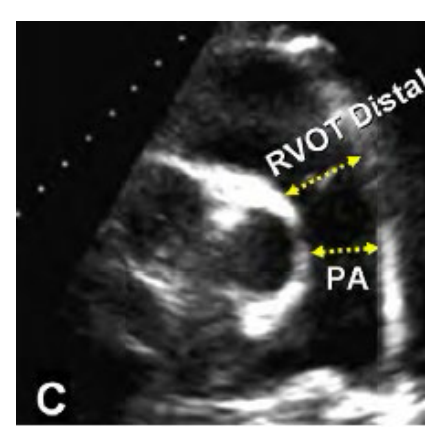

ow do you measure the RV diameter in PSAX at the great vessel view Distal, whats the abnormal diameter number?

RVOT distal diameter measured at end diastole. Inner edge to inner edge just proximal to the pulmonic valve

Abnormal is a Diameter > 2.5 cm

How is the main Pulmonary artery measured and what is the abnormal number?

Main Pulmonary artery is measured inner edge to inner edge at end diastole at the mid point.

Abnormal is > 2.0 cm